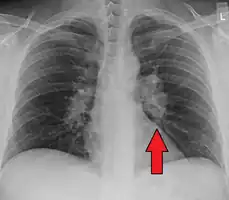

Hilar adenopathy especially on the person's left (AP CXR) -

Hilar adenopathy especially on the person's left (lateral CXR) -